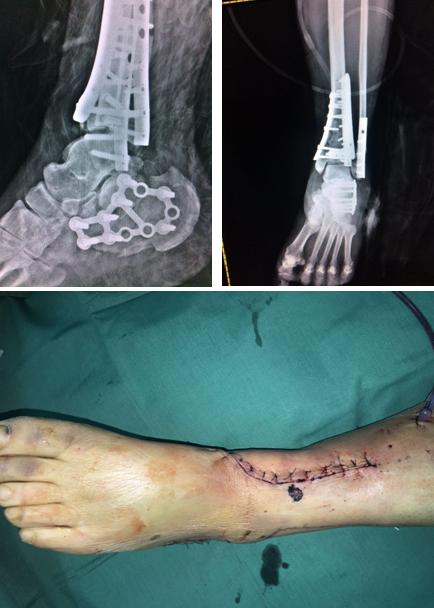

消肿半个月,手术时机到来,正值同济大学附属同济医院足踝专家俞光荣教授来sararz坐诊,俞教授看到华大姐的复杂病情后很感兴趣,决定亲自主刀手术。

术中

4月上旬,俞光荣教授和足踝科徐明亮手术小组共同为华大姐进行了“左pilon骨折及左跟骨骨折切开复位内固定术”,手术进行了4个小时,非常成功。

“患者是双pilon骨折,双跟骨骨折,腰椎部位还多发骨折,手术不能一次做完,得分期做。一次做完的话手术时间太长容易感染,病人也承受不了。”徐明亮主任说。

术后